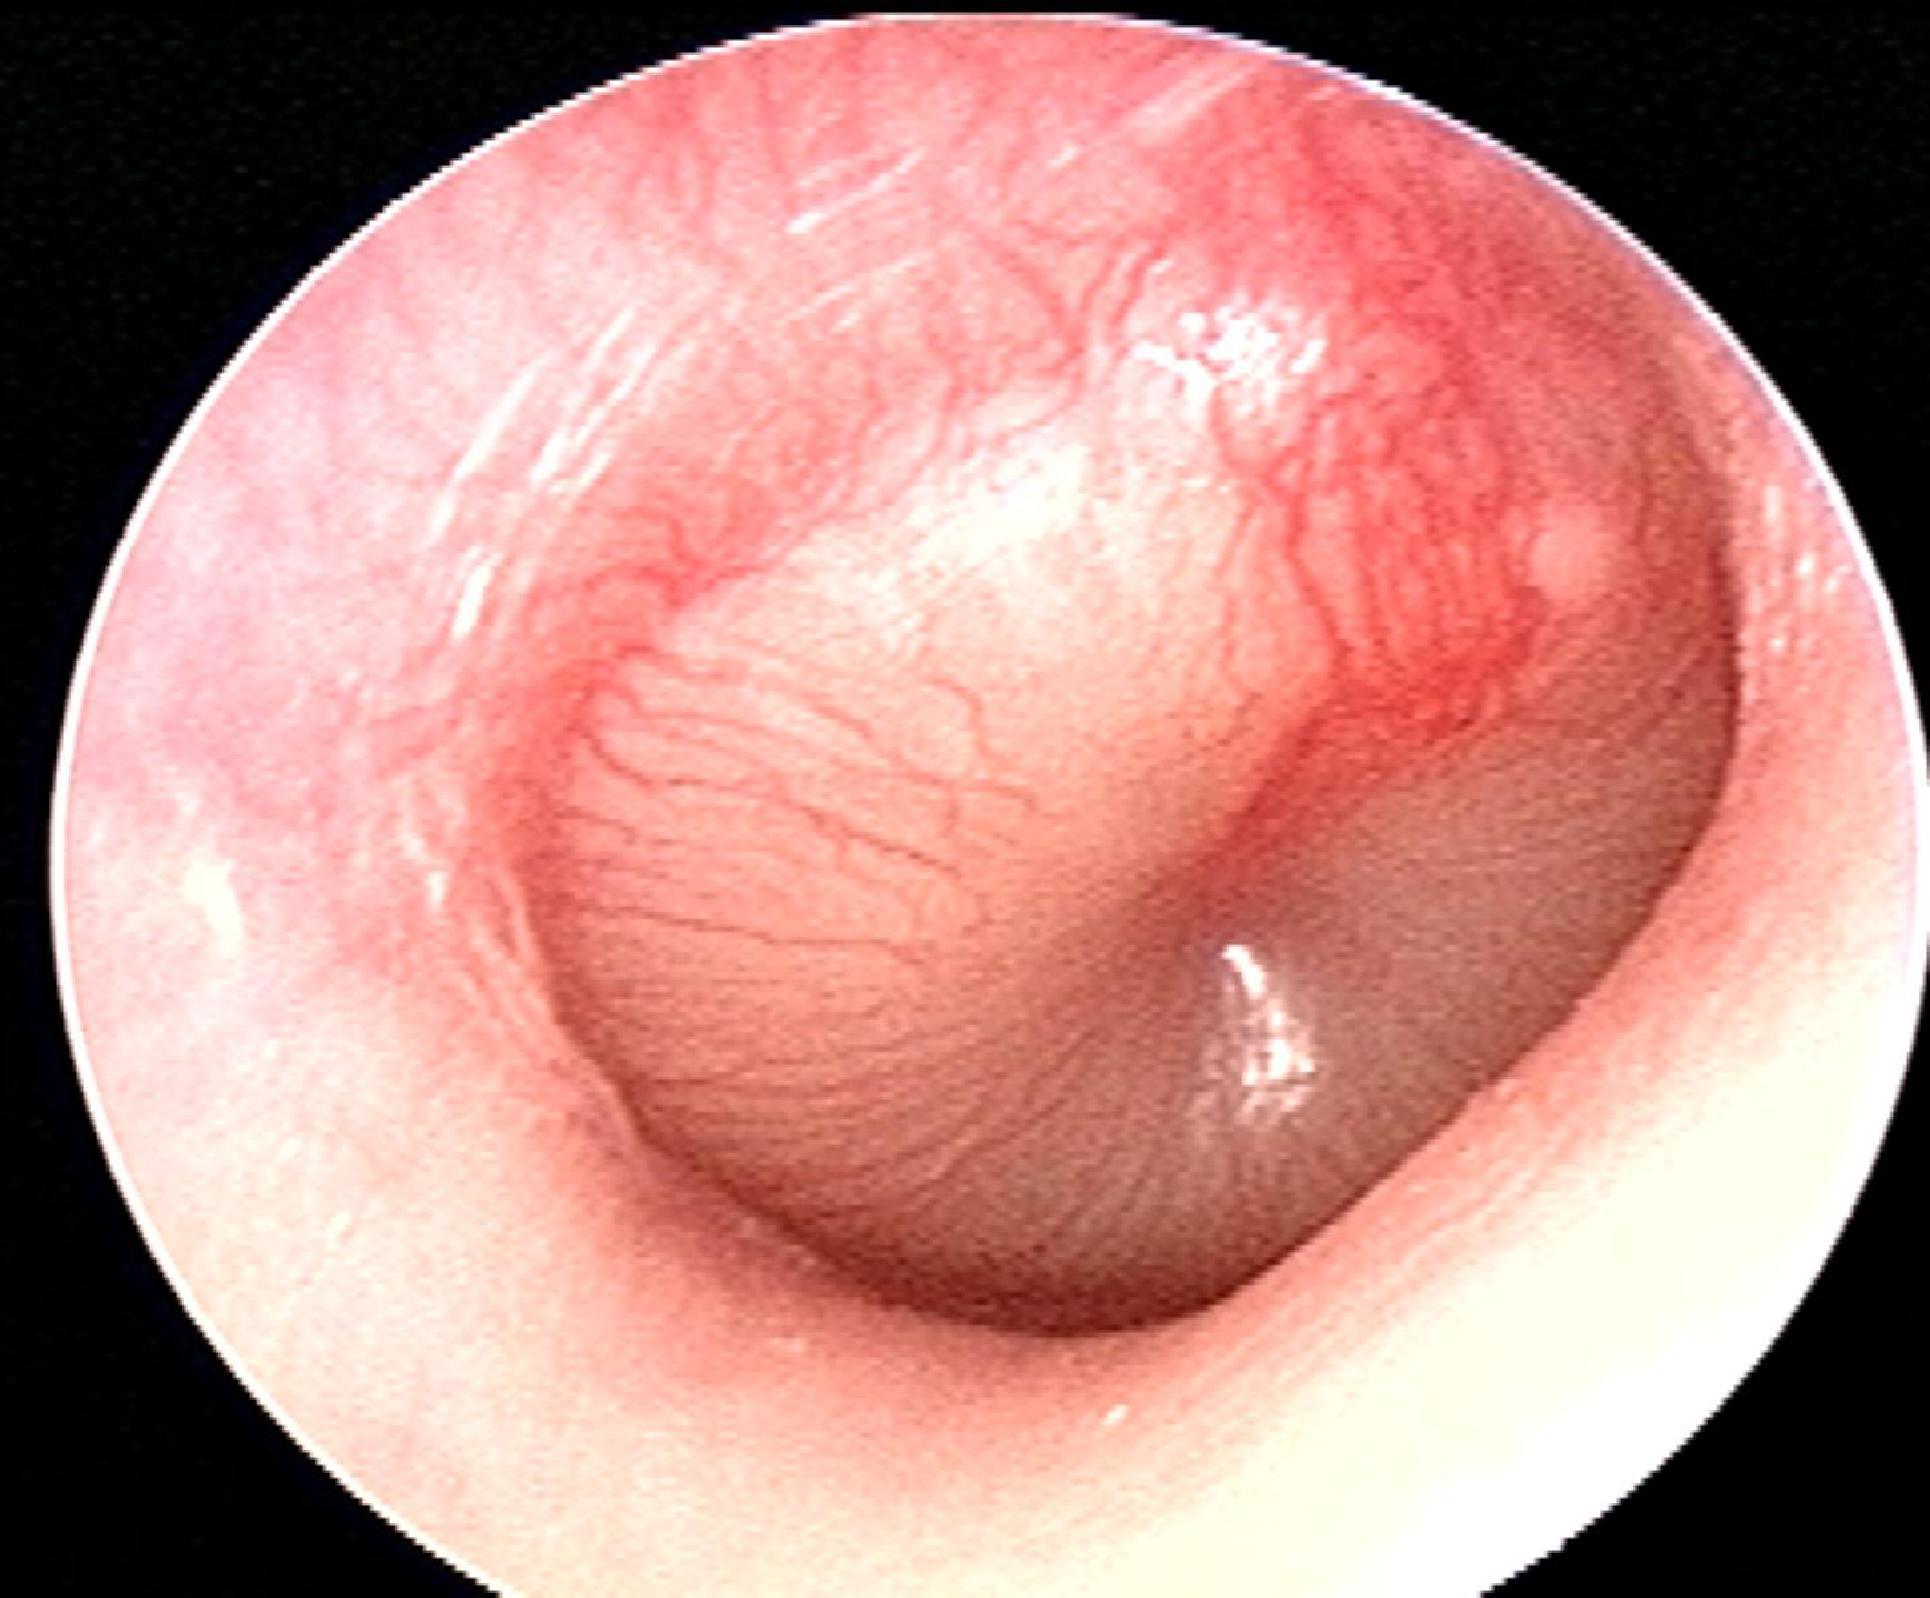

A 7-year-old boy is brought to the clinic by his parents due to right ear pain. For the past few days, the patient's parents say he has had a low-grade fever, a runny nose, and has been frequently pulling on his right ear. Past medical history is significant for a similar episode one month ago for which he has prescribed a 10-day course of amoxicillin. He is up-to-date on all vaccinations and is doing well at school. His temperature is 38.5°C (101.3°F), blood pressure is 106/75 mm Hg, pulse is 101/min, and respiratory rate is 20/min. Findings on otoscopic examination are shown in the image. The patient is treated with amoxicillin with clavulanic acid. Which of the following best describes the benefit of adding clavulanic acid to amoxicillin?